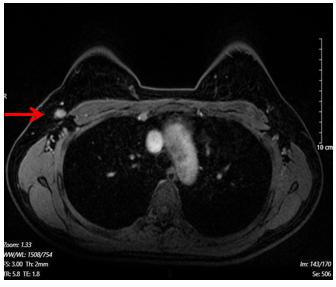

Hình 2. Hình ảnh chụp cộng hưởng từ tuyến vú. Hạch hố nách bên phải, có vỏ dày, kích thước 7x13mm (mũi tên màu đỏ)

· Hạch hố nách bên phải, chặng I có vài hạch, có vỏ dày, kích thước lớn nhất 7x13mm

+ Vú trái: Hệ thống ống tuyến cân đối, không thấy khối, không tụt núm vú, không co kéo da